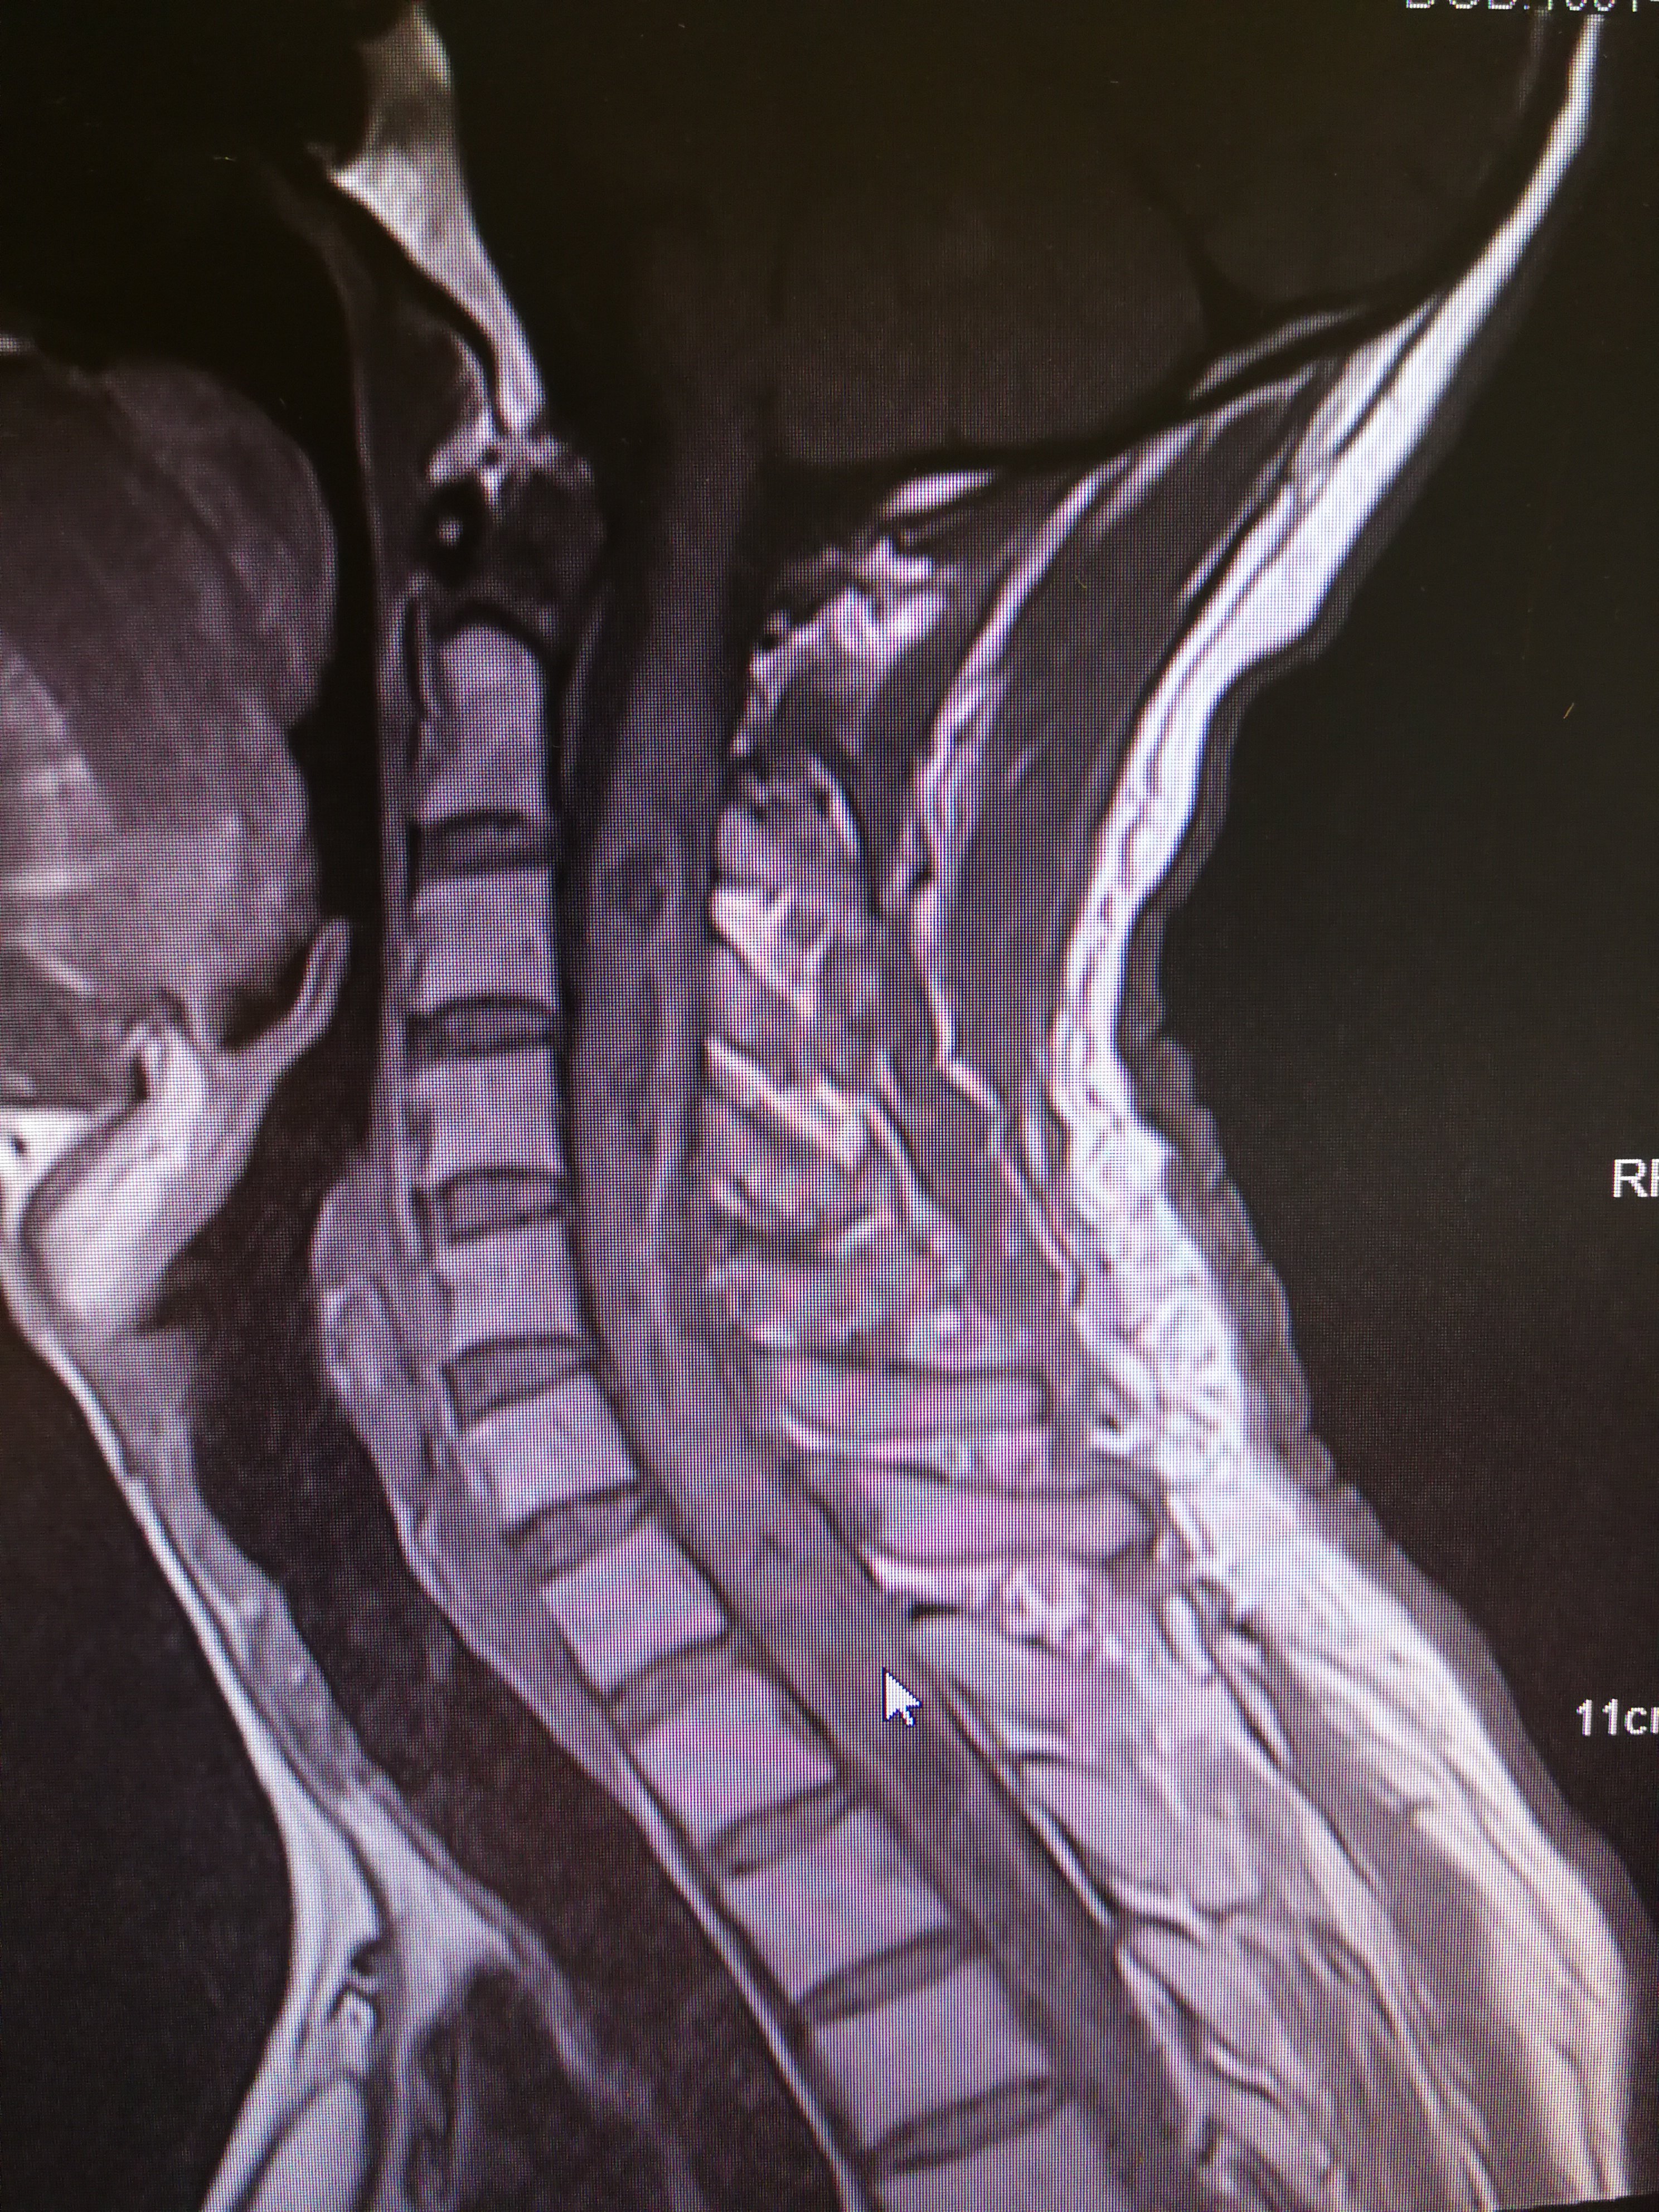

颈椎占位,请大家看看这是肿瘤还是结核